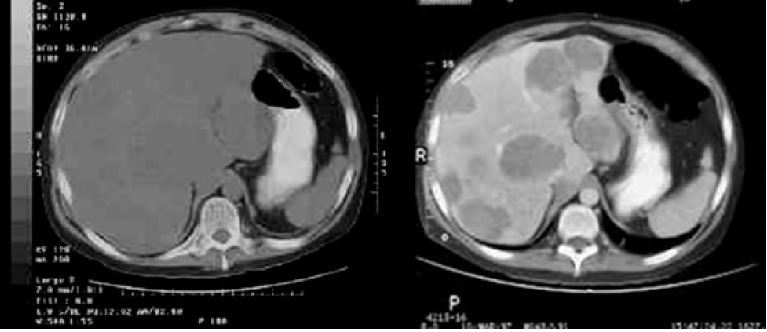

4

Q

-imaging modality -orientation -window -body part -which image has contrast? -what is abnormality?

A

-CT -axial -soft tissue -abdomen -right image; -liver tumors